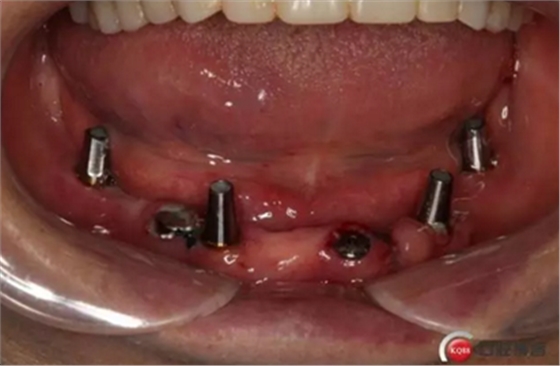

2)術前準備及手術過程,測量血壓及血糖,簽種植知情同意書;嚴格遵循無菌操作,局麻下采用微創(chuàng)技術于323436分別植入osstem4.0X10,4.0X10,4.5X7; 434446分別植入osstem4.0X1O,4.0X10,4.5X7.初期穩(wěn)定性均達到了35N.CM以上;嚴密縫合,止血,種植體位點和方向與設計一致。

4)三個月后行種植二期手術并拔除33殘冠,于34364346種植體接入成品基臺,調改活動義齒做一個改良式的套筒冠覆蓋義齒。

健康的牙齦袖口